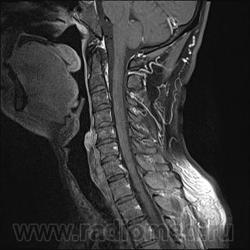

Шейный остеохондроз.Грыжа С7-Th1.Не исключено наличие миелопатии на этом уровне, но боюсь ошибиться-изображения мелковаты ,идаже кажется, что есть повышение МРС от спинного мозга по Т1( скорее всего-артефакты?).

Левосторонняя парамедианная с компрессией корешка.

а это не перидурит??? смотрели месяц назад (в начале заболевания) было меньше.

Посмотрите на STIRе. Если жидкости нет, то простая грыжа. На этих сканах вообще-то жидкости не видно. За месяц грыжа могла и подрасти, смотря как лечили.

По-моему, только грыжа.